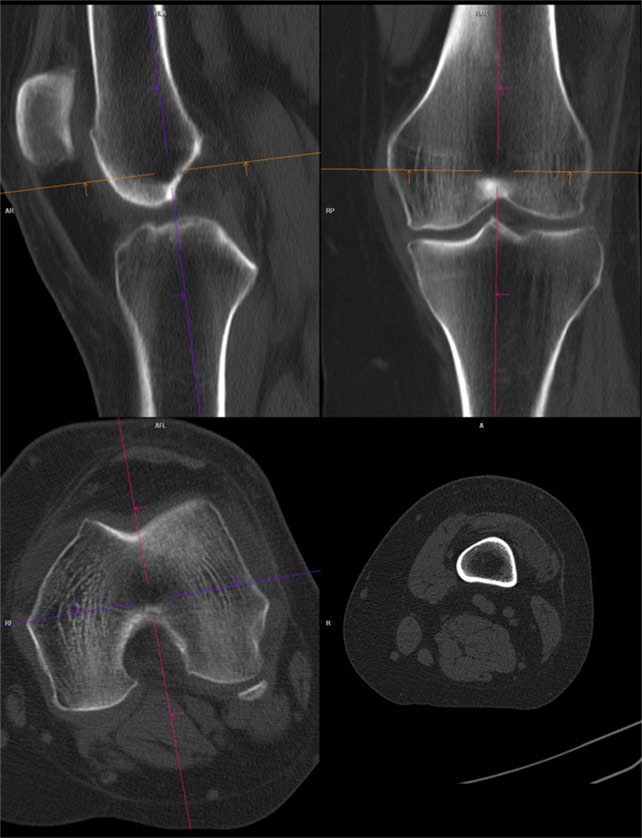

De obicei, pentru articulatii/ oase, se folosesc imagini cu doua tipuri de parametri diferiti: pentru parti moi si pentru os.

Imaginile cu parametri de os (“kernel” dedicat osului) sunt cu conturi mult mai netede, mai exacte, mai “sharp”, care permite o foarte bună apreciere a celor mai fine traiecte de fractură, însă imaginile 3D obținute pe seama acestora nu sunt la fel utile, fiind cu margini ascuțite și un aspect mai puțin plăcut vizual datorită prea multor detalii prezente.

Reconstrucții în alte planuri (MPR)